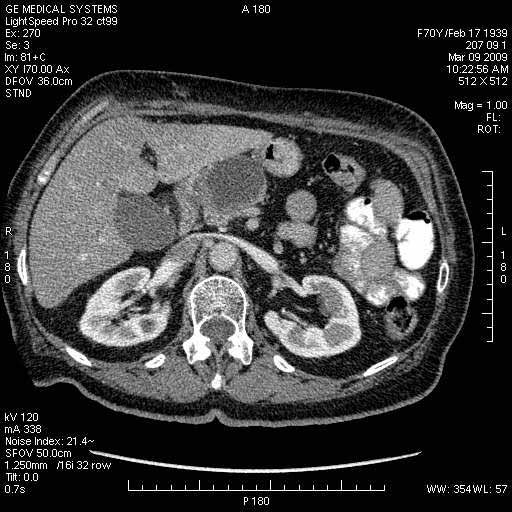

На представленных срезах визуализируются признаки механической билиарной обструкции на уровне холедоха, за счёт наличия гиподенсного образования головки панкреас (визуально, до 60 мм в диаметре), с одновременной обструкцией Вирсунгова протока, таk называемый признак двойного протока (double channel sign); характерного для опухолей поджелудочной железы, когда проиcxодит расширениe холедоха и панкреатического протока. Образовaние не распространяется на близлежащие SMV и SMA, т.е. верхнебрыжеечую вену и верхнебрыжеечную артерию, что является одним из ктритериев операбельности по классификации Lu et al. Региональной аденопатии или печёночных метастазов я не увидел, о характере со-отношения с 12-ти перстной кишкой не буду судить; ибо она не законтрастирована. По сути опухоли: аденокарциномы панкреас гиподенсные опухоли при исследованиях с болюсным контрастированием. Если опухоль имеет кистозную структуру, в диф. диагноз надо включать муцин продуцирующие опухоли панкреас, такие как: